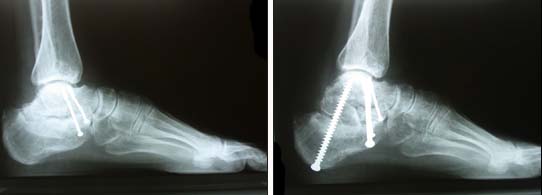

Nel piede gli assi delle ossa delle articolazioni sono essenziali per una funzione efficace. L’orientamento osteo-articolare è primordiale. Nel caso di malunione conseguente alla frattura articolare, per esempio del calcagno, soprattutto se non è stata corretta dopo il trauma, la ricostruzione chirurgica consiste nel ripristino degli assi osteo-articolari, insieme a un bloccaggio delle articolazioni distrutte. Questo intervento complesso può richiedere un eventuale innesto di ossa prese dal paziente.